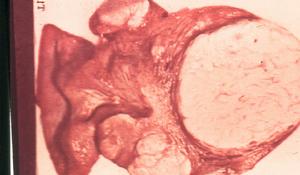

子宮平滑肌瘤良性腫瘤和惡性腫瘤的主要區別大致有如下幾點: 良性腫瘤的生長速度緩慢,惡性腫瘤長得比較快;良性腫瘤不發生轉移,惡性腫瘤很容易轉移;良性腫瘤質地一般較軟,多數有包膜和周圍組織相隔,觸診腫瘤時,腫瘤有一定的活動度,表面較光滑,手術切除時,容易治癒,一般無全身症狀;